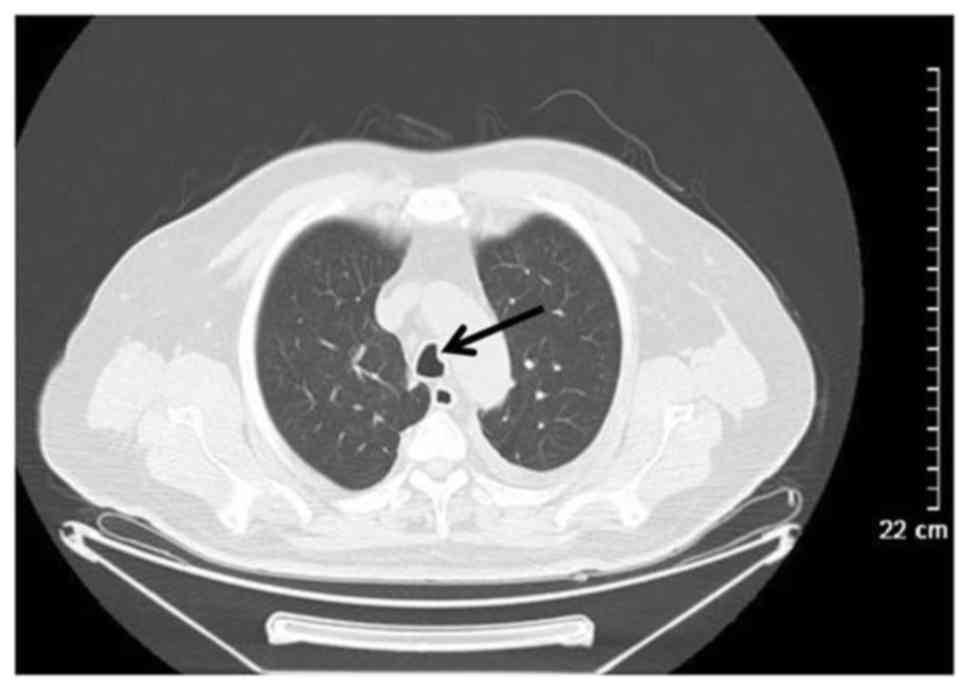

Thoracic Manifestation Of Wegener's Granulomatosis: Computed Tomography

Thoracic manifestation of Wegener's granulomatosis: Computed tomography www.spandidos-publications.com

computed granulomatosis tomography wegener misdiagnosis findings manifestation thoracic analysis etm